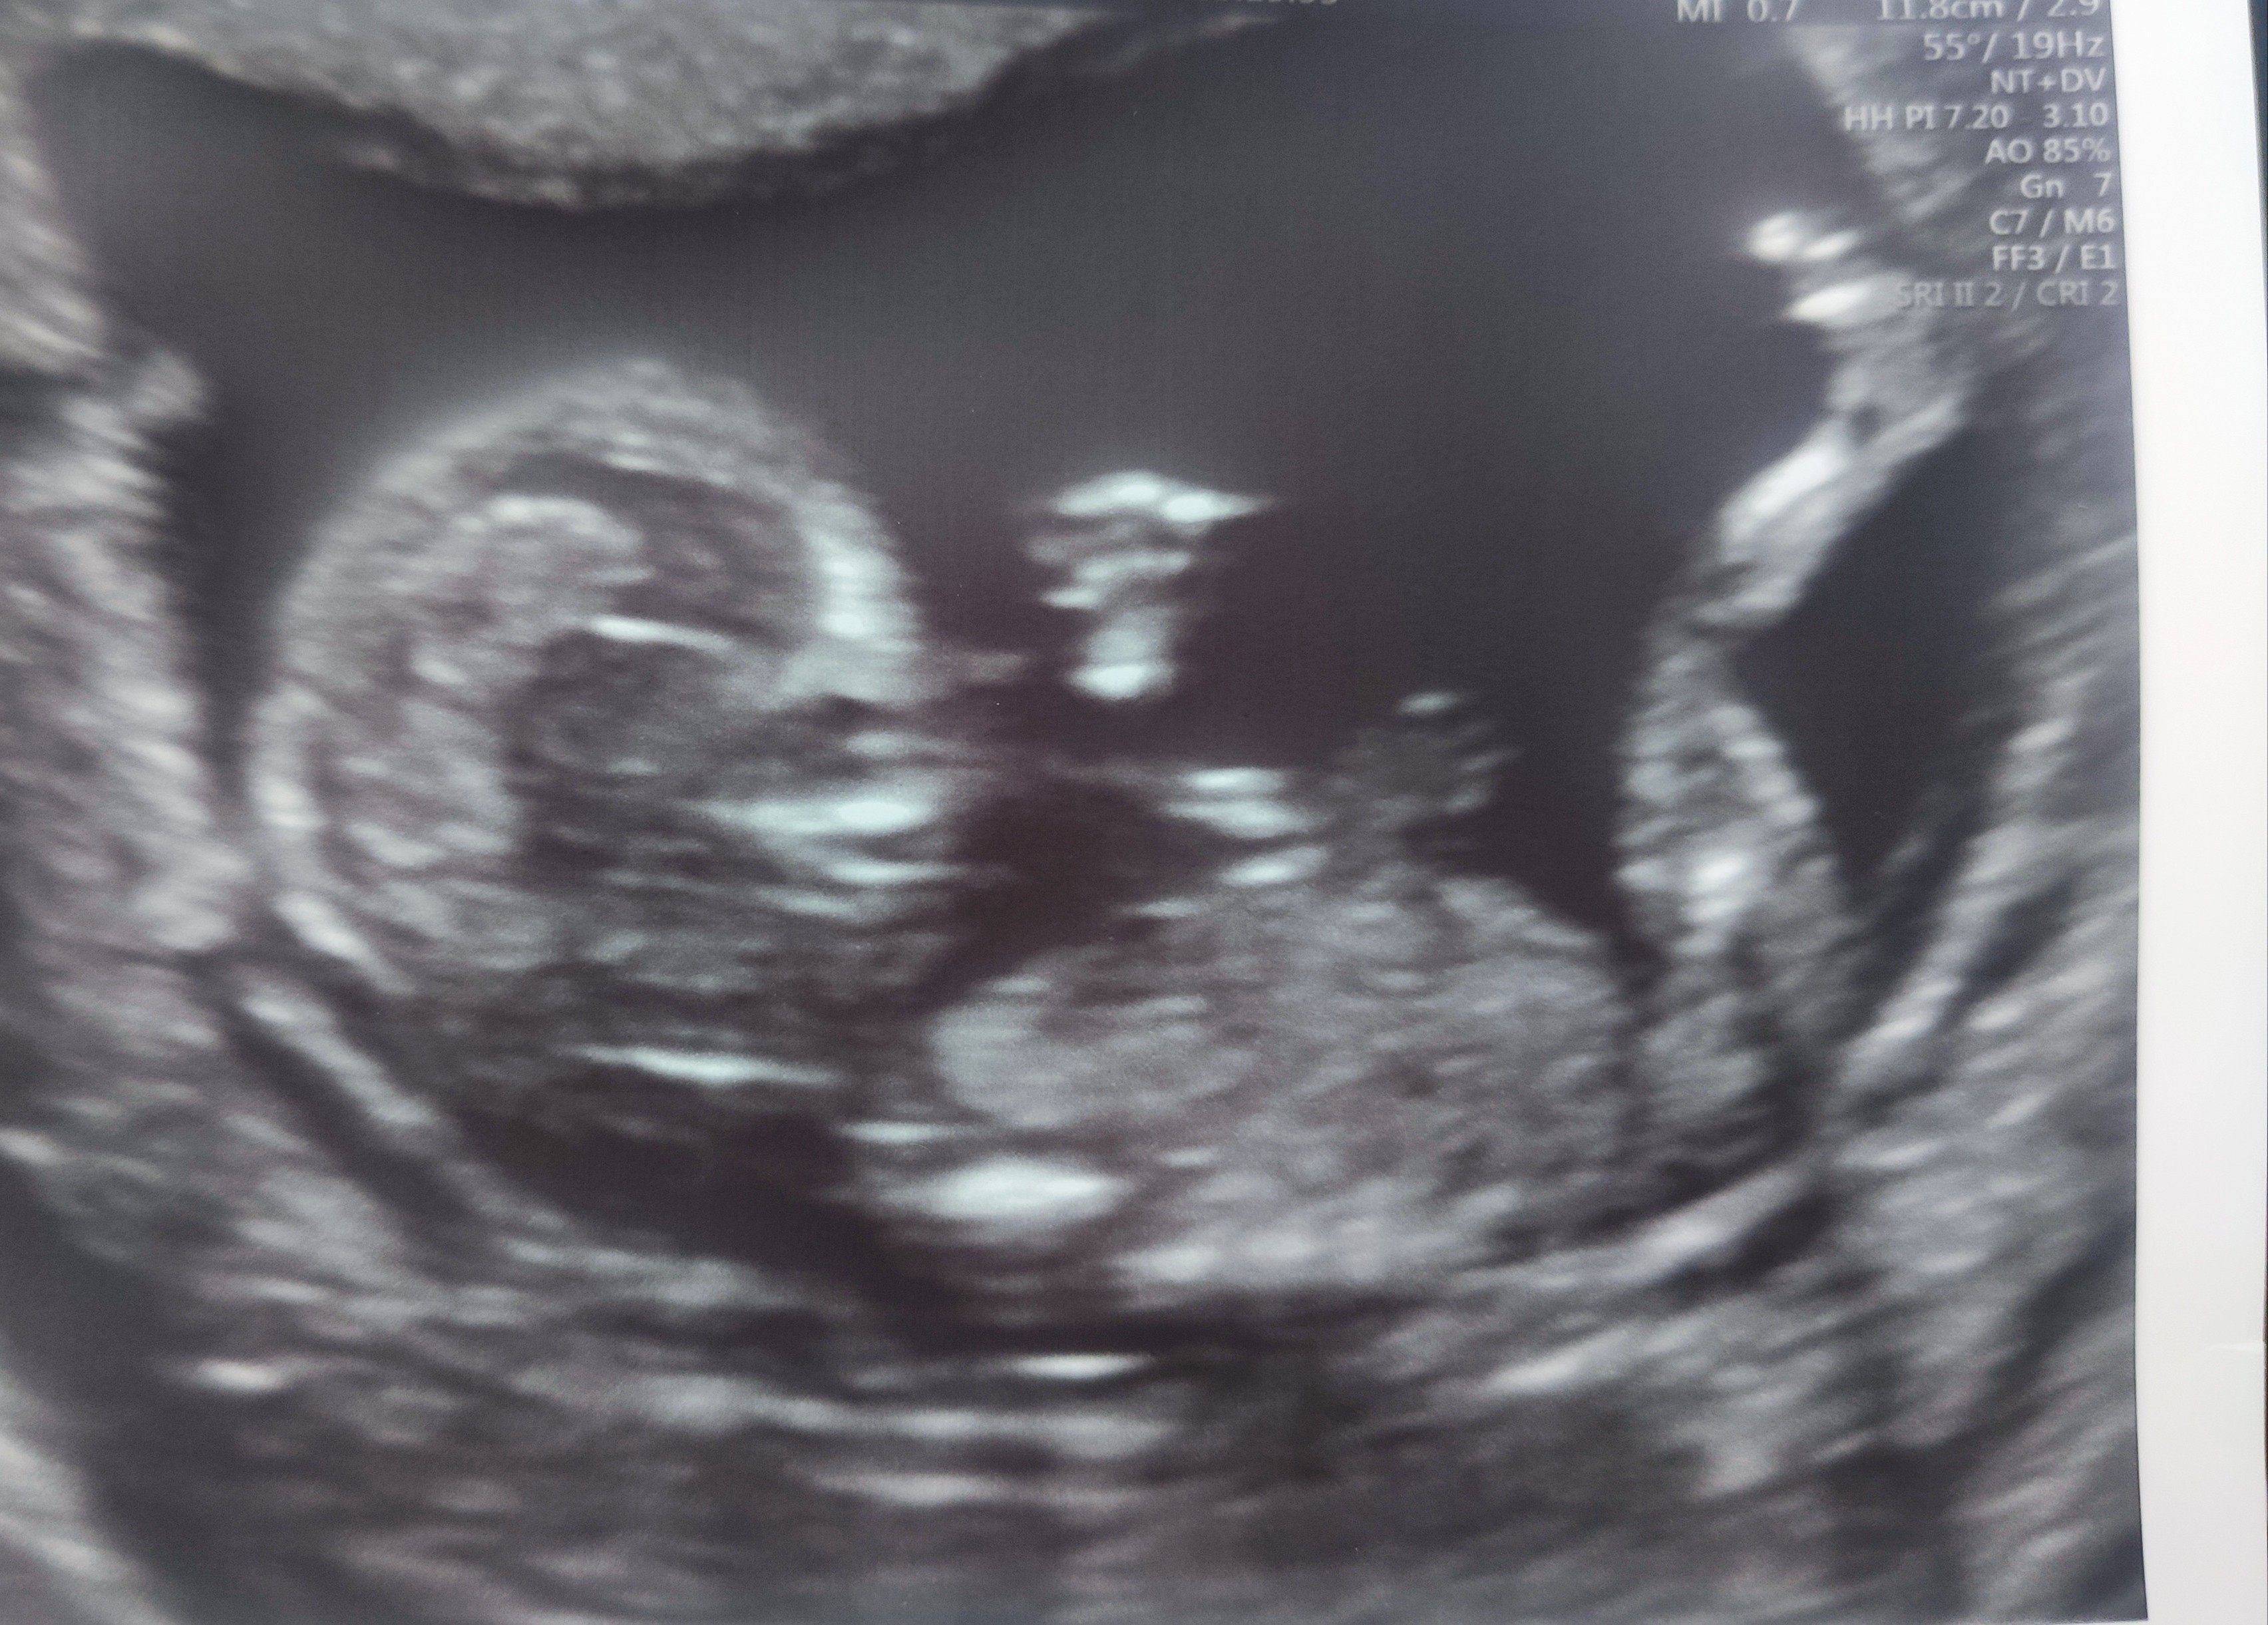

Hej! Ja wczoraj miałam prenatalne (było 12+4).

Bąbelek ma 6,1 cm. Wszystko jest ok- parametry wręcz książkowe. Dziwi mnie tylko że taki mało ruchliwy ten dzidziuś bo tylko nogami i rękoma ruszał ale pozycja taka sama jak dwa tygodnie temu 🙈 może po prostu jest leniuchem i caly czas leży na plecach... 😅

Wyniki z krwi będę miała za jakieś 2 tygodnie.

Zobacz załącznik 1155356